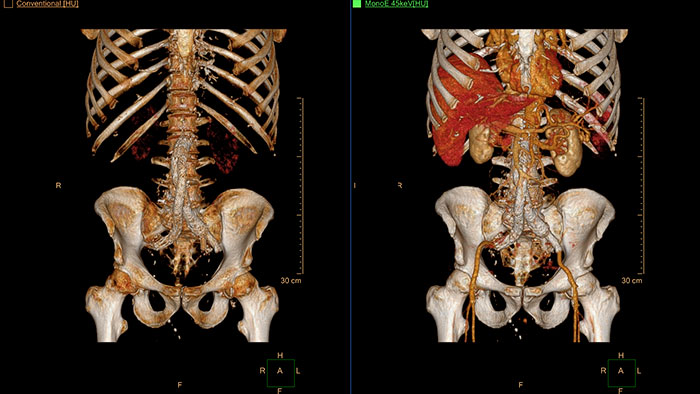

Streamlined modeling workflow

Allows to view volumetric images of anatomical structures, perform segmentation, edit and combine segmented elements (tissues) into a 3D model.

*3D models are not intended for diagnostic use.